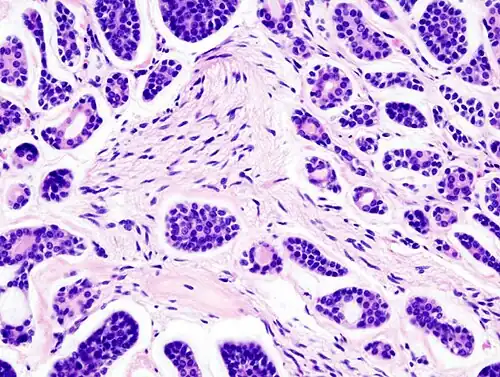

Micrograph of an adenoid cystic carcinoma of a salivary gland (right of image): Normal serous glands, typical of the parotid gland, are also seen (left of image), H&E stain. | |

Histopathological image of adenoid cystic carcinoma of the salivary gland infiltrating a nerve (center), H&E stain